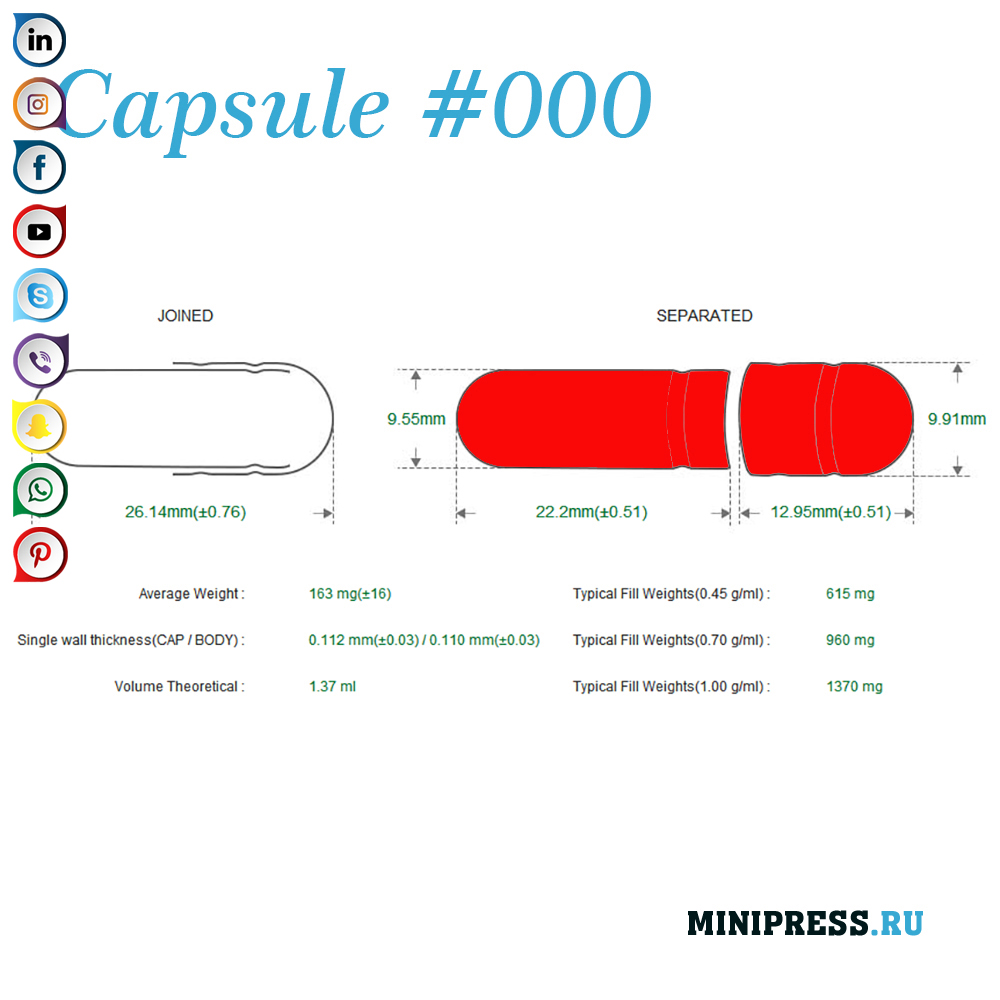

Velike zelatinskih kapsula: 000,00,0,1,2,3,4,5, A, B, C, D, E.